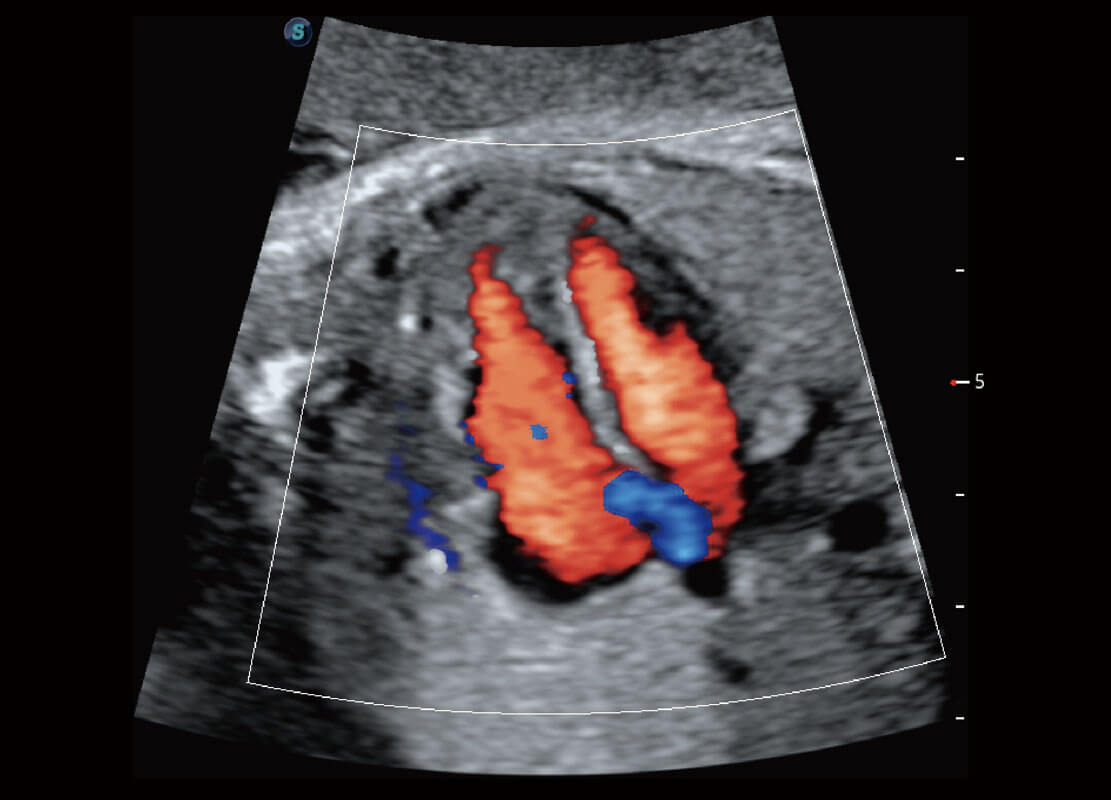

P60搭載一系列胎兒心臟成像技術(shù),實現(xiàn)精細的胎兒心臟評估。

四腔心血流